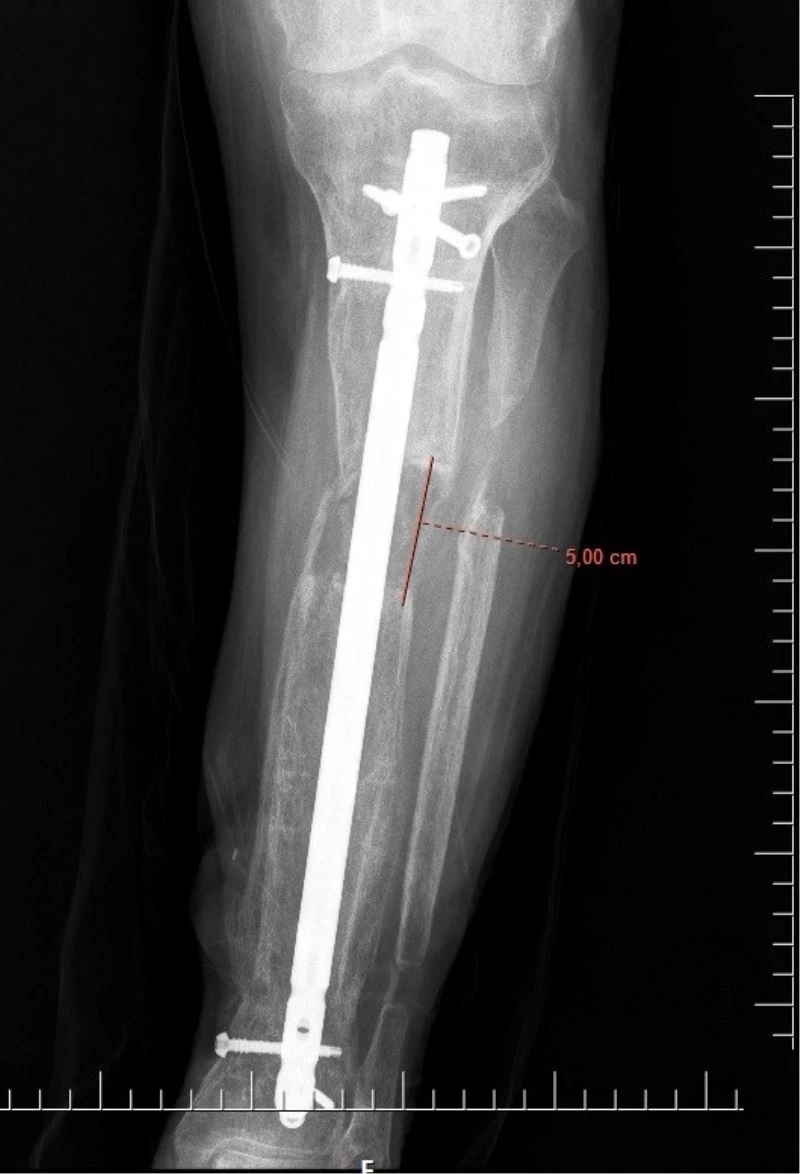

İsmi açıklanmayan bir erkek hasta, 5 yıl önce iş kazası geçirdi. Hastanın kaval kemiğinde parçalı kırıklar oluşması sonucu bacağı diğerine kıyasla kısaldı. 5 yıl boyunca aksayarak yürümek zorunda kalan hasta, Elbistan Devlet Hastanesi’ne başvurdu. Ortopedi servisinde Ortopedist Op. Dr. Ali Canbay ve Op. Dr. Serdar Karaman tarafından tetkikleri yapılan hastaya, boy (kemik) uzatma operasyonu yapılması kararlaştırıldı. Hastanın bacağına, ilk ameliyatında kısa olan kemiği günde 1 mm uzatma olacak şekilde bir sistem kuruldu. Başarılı geçen operasyon sonrasında kurulan sistem sayesinde 5 cm uzama ve yıllardır kaynamayan kemikte kaynama elde edildi. Son olarak dışarıdan uygulanan bu sistem çıkarıldı ve uzamanın kontrol altına alınması için çivi denilen işlem uygulandı. Hasta, tüm bu işlemlerin akabinde aksamadan yürümeye başlayarak eski sağlığına kavuştu.

Operasyonla ilgili Elbistan Devlet Hastanesi’nden yapılan açıklamada; “İş kazası nedeniyle beş yıl önce kaval kemiğinde parçalı kırığı olan ve kırık olan bacağında diğer bacağına kıyasla kısalığı devam eden hastamıza, Elbistan Devlet Hastanesi’nde Ortopedist Op. Dr. Ali Canbay ve Op. Dr. Serdar Karaman’ın birlikte yaptıkları iki operasyon sonucu hasta eski sağlığına kavuşmuştur. İlk ameliyatında kısa olan kemiği günde bir milimetre uzatma olacak şekilde kurulan sistem ile 5 cm uzama ve yıllardır bir türlü kaynamayan kemikte kaynama elde edilmiştir. Son olarak dışarıdan uygulanan sistem çıkarılıp hastanın konforlu hayatına dönmesi için çivi denilen işlem ile mevcut uzamanın koruma altına alınıp hastanın tekrar aksamadan yürümesi sağlanmıştır” denildi.